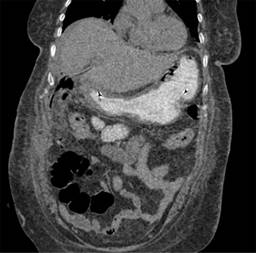

Se trata de paciente femenino de 59 años, que cuenta con antecedente de diabetes mellitus tipo 2 de larga evolución. Acude al servicio de urgencias por presentar dolor de tipo cólico en hipocondrio derecho de seis meses de evolución, de intensidad 6/10 en la escala análoga visual, sin irradiaciones, asociado a la ingesta de alimentos colecistoquinéticos, sin atenuantes, niega fiebre, ictericia, coluria o acolia. A la exploración física, con dolor a la palpación profunda en hipocondrio derecho, Murphy ausente, sin datos de irritación peritoneal. Cuenta con los siguientes laboratorios: hemoglobina 12.9 g/dl, hematocrito 37%, leucocitos 9.4 × 103/μl, plaquetas 360 × 103/μl, glucosa 178 mg/dl, creatinina 0.7 mg/dl, sodio 145 mEq/l, potasio 3.7 mEq/l, cloro 105 mEq/l, bilirrubina total 0.7 mg/dl, fosfatasa alcalina 55 U/l. Se realiza ultrasonido de hígado y vías biliares, el cual revela vesícula biliar con aumento de su ecogenicidad en toda su extensión, provocando fenómeno Wall-Echo-Shadow (WES) con dimensiones de 52.7 × 29.4 × 18.7 mm. Con pared no valorable, colédoco de 5.8 mm, sin evidencia de litos en su interior (Figura 1). Se realiza rastreo tomográfico donde se observa vesícula con volumen de 13.2 cm3, heterogénea, con presencia de densidad aire, pared engrosada de manera regular con presencia de calcificaciones, estómago distendido, con presencia de imagen hiperdensa en su interior (probable lito) (Figura 2).

Figura 1: Ultrasonido de hígado y vías biliares. La flecha indica engrosamiento de pared vesicular y escleroatrófica.